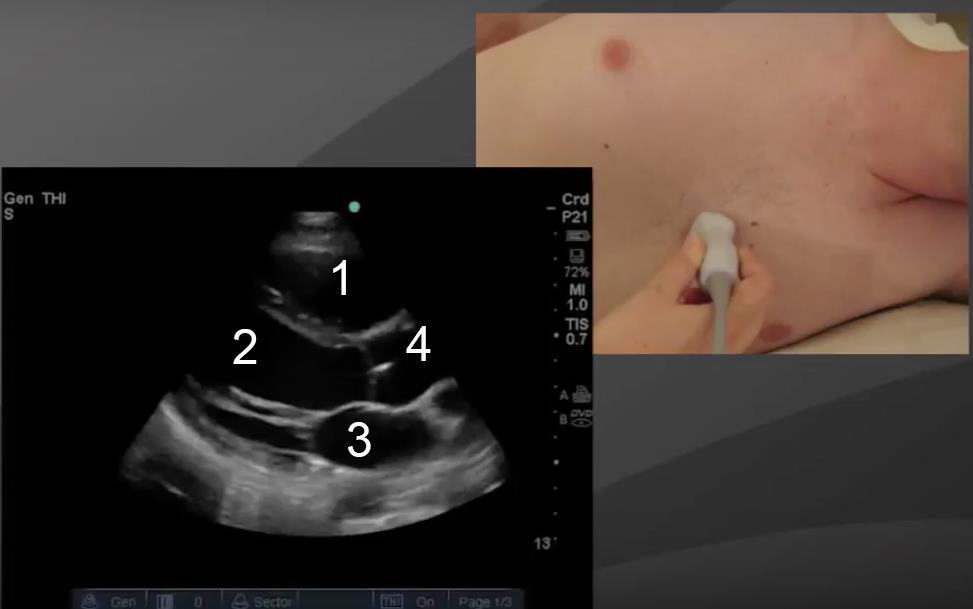

Bild 1: Ansicht des Herzes auf parasternaler langer Achse (PLAX)

1. Rechter Ventrikel (RV)

2. Linker Ventrikel (LV)

3. Linkes Atrium (LA)

4. Aorta